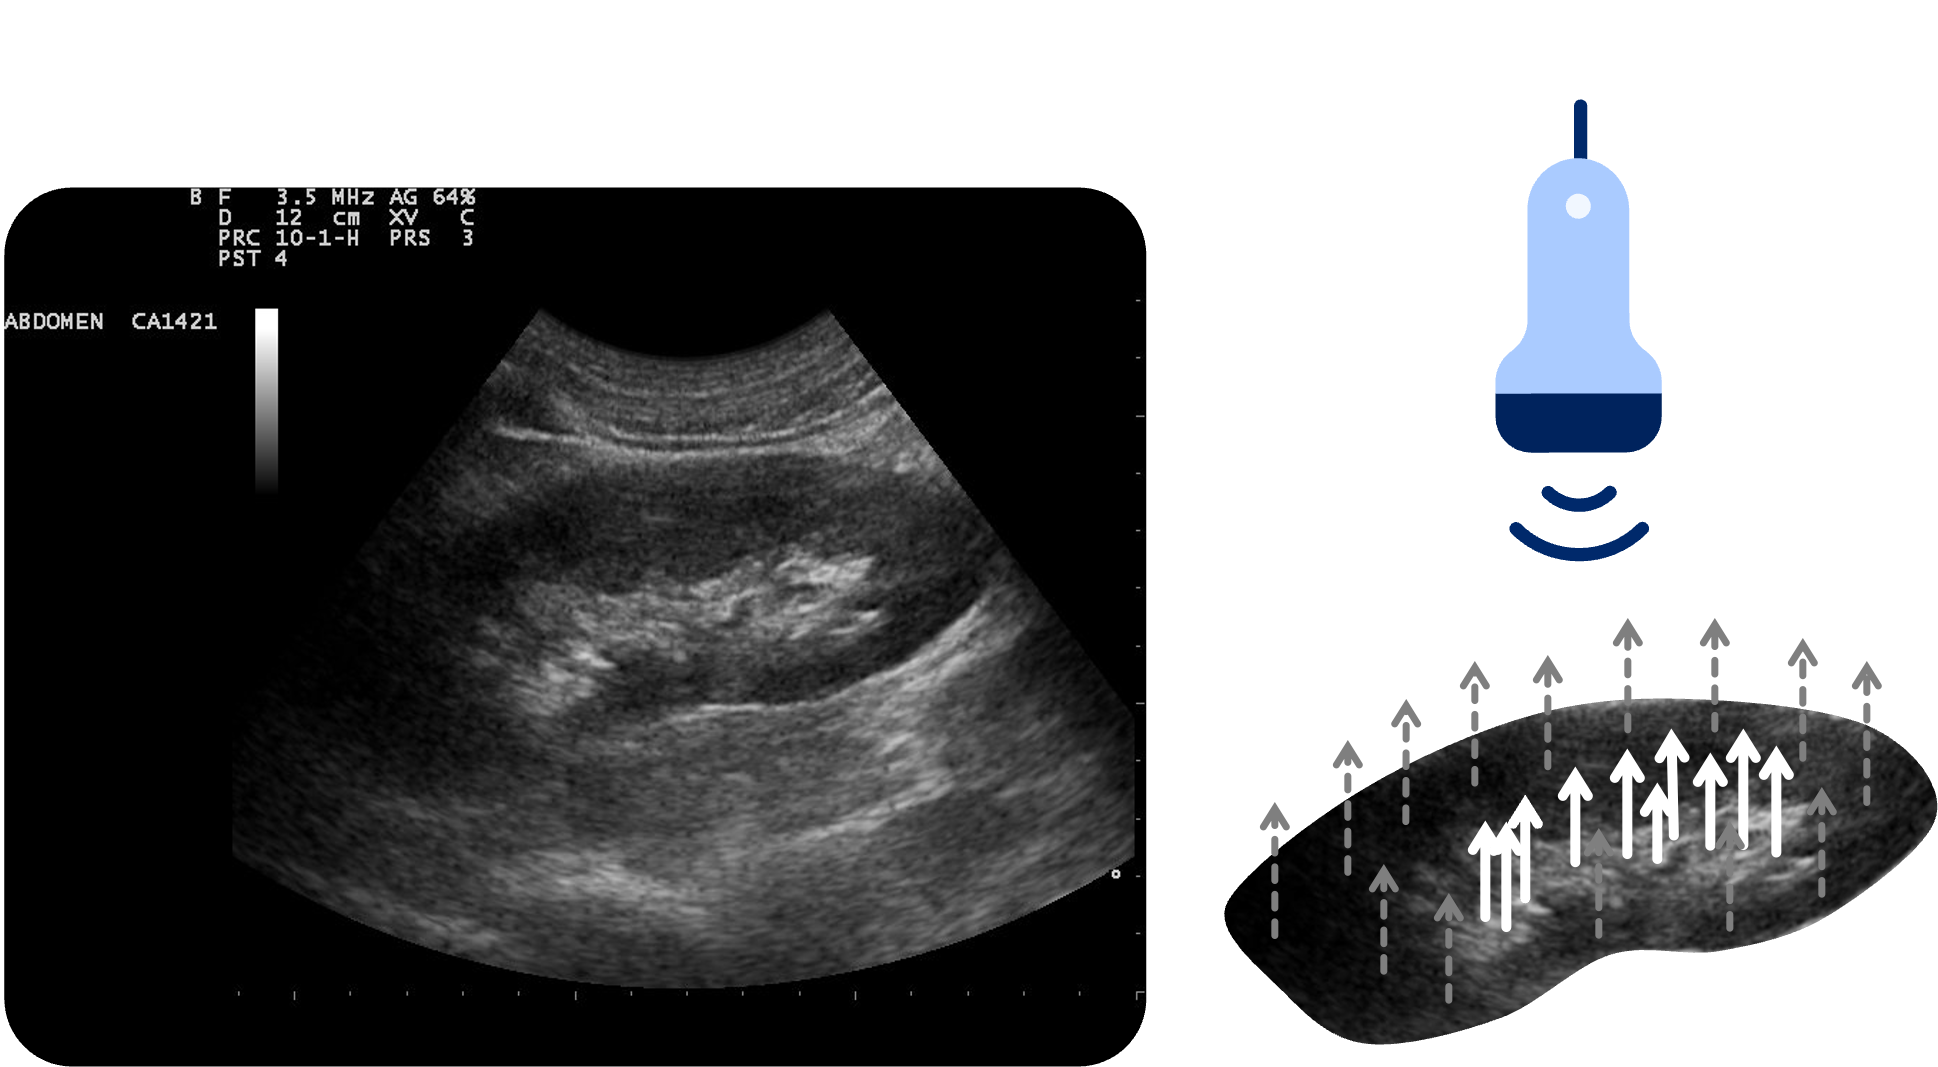

Distale Schallverstärkung:

Dieses Artefakt entsteht, wenn der Schall ein schwach dämpfendes Medium durchquert – typischerweise Flüssigkeit. Da Flüssigkeit den Schall kaum absorbiert oder streut, erreicht mehr Schallenergie das dahinterliegende Gewebe. Dieses reflektiert entsprechend stärkere Echos, die im Bild als hellere Zone distal der Flüssigkeit sichtbar werden. Dieser Effekt findet sich häufig hinter Gefäßen, Zysten, der Harnblase oder Aszites.

Physikalische Grundlagen:

In homogenem Gewebe nimmt die Schallintensität aufgrund von Absorption und Streuung mit zunehmender Tiefe ab

Flüssigkeiten verursachen nahezu keinen Energieverlust, sodass der Schall mit vergleichsweise höherer Intensität tiefer gelegene Strukturen erreicht

Das Gerät geht jedoch von einer gleichmäßigen Dämpfung aus und interpretiert die starken Echos aus der Tiefe als echoreichere Strukturen. Sie werden daher heller dargestellt

Die distale Schallverstärkung kann in vielen Situationen sehr hilfreich sein. In der Regel bestätigt sie uns, dass eine Struktur flüssigkeitsgefüllt ist und kann so bei der Abgrenzung von Differentialdiagnosen eingesetzt werden, z.B. Zyste vs. Tumor.